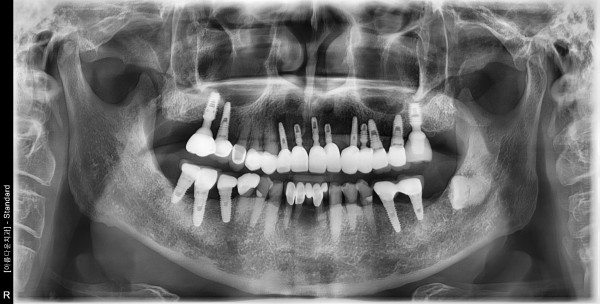

70대 남성 임플란트 식립

2d74e31fb819137f530da93a17333eb6_1759282